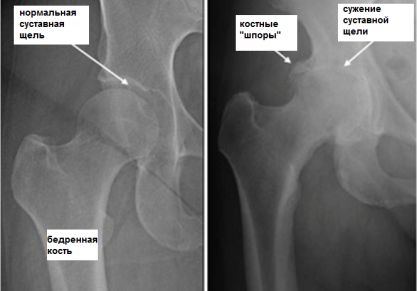

• Коксартроз — артроз тазобедренного сустава. Данная разновидность заболевания является лидирующей.